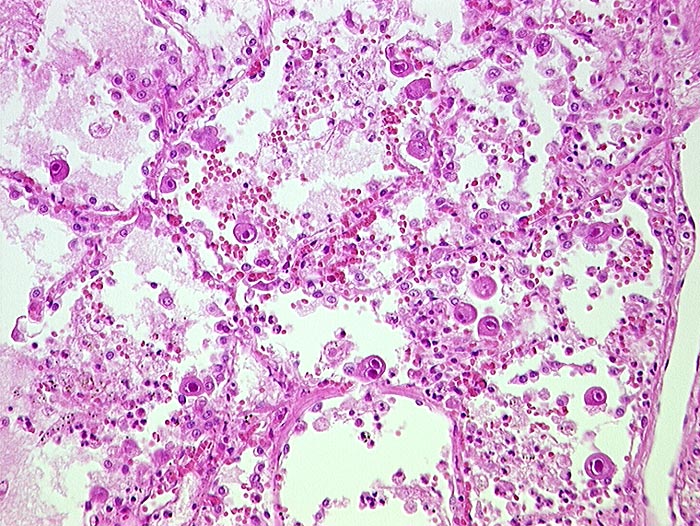

PathoPic – image database / PathoPic ID 215 - CMV (Zytomegalie) Pneumonie

CMV (Zytomegalie) Pneumonie

Virale Kerneinschlüsse mit Halo in Pneumozyten (sogenannte Eulenaugenzellen)

HIV positiv seit 5 Jahren. Nachweis von zytomegalen Zellen im Hirn, in der Lunge, im Gastrointestinaltrakt, den Nieren und der Nebenniere. Zusätzlich bakterielle Pneumonie.